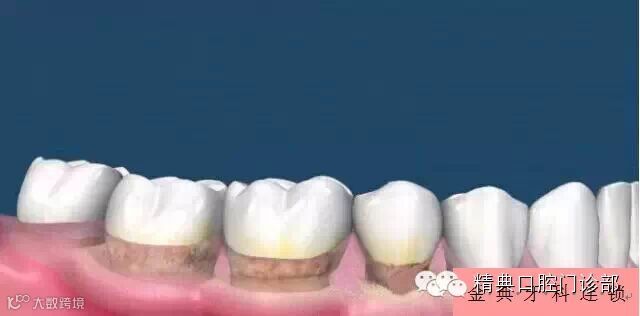

图片一、您以前有一口健康漂亮的好牙。

图片二、时间长了,您的牙面上滋生牙菌斑和牙结石。

图片三、当牙菌斑和牙结石累计一定程度时,牙龈开始变得红肿。

图片四、牙菌斑和牙结石没有被及时的清除,牙龈进一步的红肿,这是您会发现牙龈偶尔有出血。

图片五、此时在牙龈以下也同样存在着坚硬的牙结石。这些牙结石开始刺激牙槽骨,牙槽骨害怕了,向后退缩,导致牙根开始慢慢暴露出来。

图片六、牙龈以下的牙结石得寸进尺,越来越多,扩大地盘,这进一步刺激牙槽骨,导致大量的牙槽骨向下退缩,牙槽骨遭到破坏,牙根露出更明显。